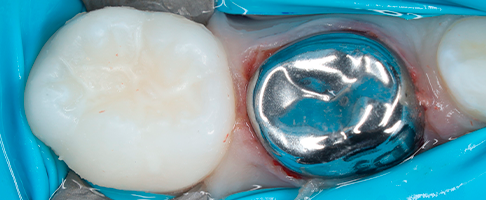

- восстановление молочных жевательных зубов коронками.

В работе доктор применяет современные биосовместимые материалы, а также изоляционную систему коффердам. Ведет фотопротокол для контроля качества работы и наблюдения результатов лечения в динамике.